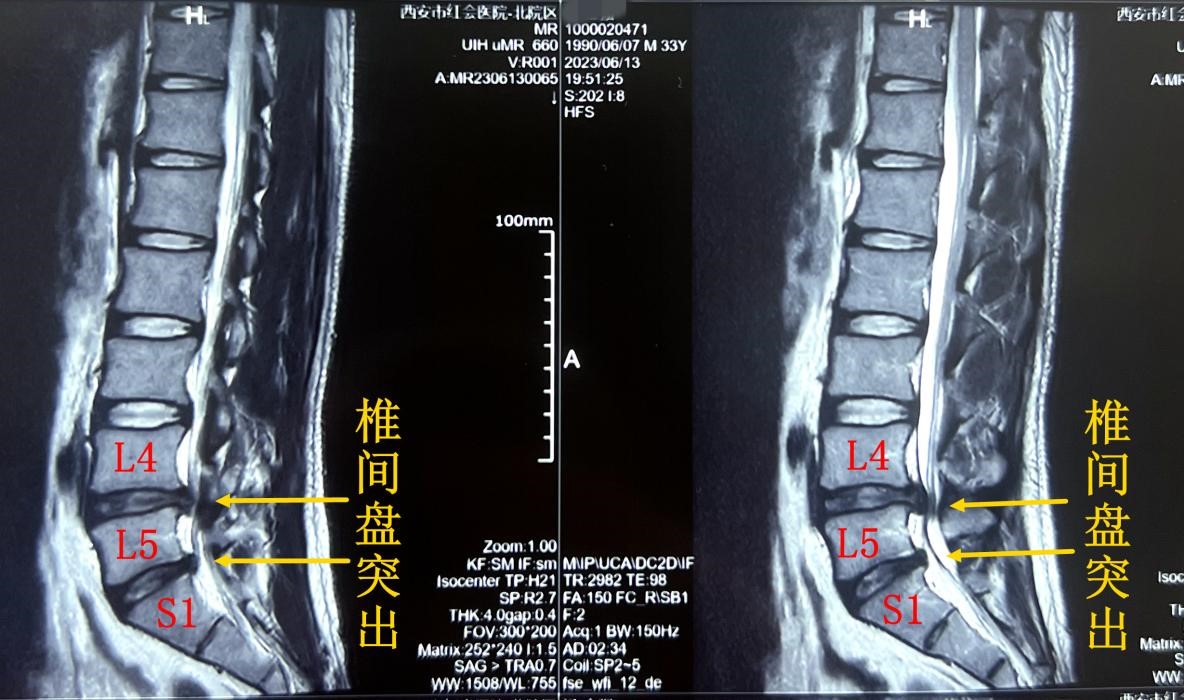

患者术前影像检查资料

患者就诊后,影像学检查显示腰4-5和腰5骶1两个节段均存在突出。其中腰4-5椎间盘突巨大突出,双侧神经根受压。

脊柱病医院院长郝定均及脊柱病医院腰椎病区主任刘团江查房后指出:患者腰椎管狭窄较重,双侧均有神经压症状,治疗需要完成双侧减压,才能达到治疗目的!传统的手术方式创伤较大、患者恢复时间更长。鉴于患者年龄轻,结合病史、体征、影像资料和查体表现等结果后制定单侧椎板入路双侧椎管减压手术(Unilateral laminotomy for Bilateral Decompression,ULBD)。